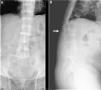

We present the case of a 55-year-old male patient who had been referred to our consultation to evaluate chronic thoracolumbar pain. Findings of the physical examination included an important reduction in spinal column mobility and grey-brown pigmentation of both sclerae. After the radiology study (Fig. 1), we decided to measure HGD levels in urine (4218.0mg/L; normal<10mg/L), which confirmed the suspected diagnosis of ochronosis. The patient began with physical therapy sessions, and the improvement was noticeable. At that time (January 2004), dual-energy X-ray absorptiometry was used to determine the bone mineral density (BMD) of the lumbar spine (LS), which showed a T-score of −3.0 SD. The patient initiated treatment with risedronate (75mg weekly). In March 2005, BMD was evaluated once again, with a T-score of −2.4 SD in the LS, −30 SD in the femoral neck (FN) and −2.7 SD in the total hip (TH). Treatment was continued with bisphosphonates, and then changed to alendronate (70mg weekly). In June 2007, BMD showed improved T-scores in the LS (−1.7 SD) and TH (−2.3 SD) and stabilization in the FN (−3.0 SD). In January 2013, the patient came to our emergency department with acute back pain, but reported having had no trauma. Lateral LS radiography revealed a fracture of the third lumbar vertebra (Fig. 1). After that incident, we opted to begin treatment with subcutaneous teriparatide. To date (November 2014), no new vertebral fractures have appeared.